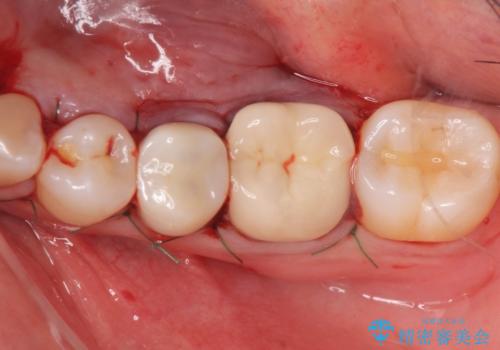

骨隆起除去

治療症例の内容

- 骨隆起が舌にあたり不快感があるので骨隆起をとりたくて来院。

静脈内鎮静麻酔下で骨隆起を除去を行いました。

骨隆起がなくなり不快感がなくなり大変満足して頂けました。